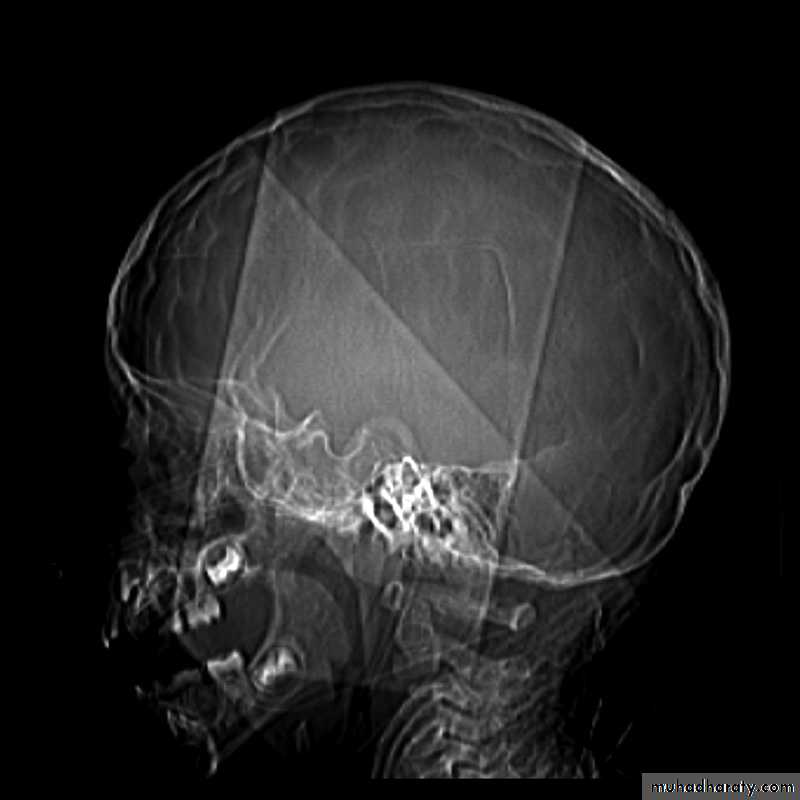

Skull X-ray findings in increased intracranial pressure

• Sutural separation in children.

• ‘Copper-beating’ marking of the cranial vault.

• Thinning of dorsum sellae.

• Erosion of the posterior clinoid process.

Copper-beating’ marking

Neurosurgery